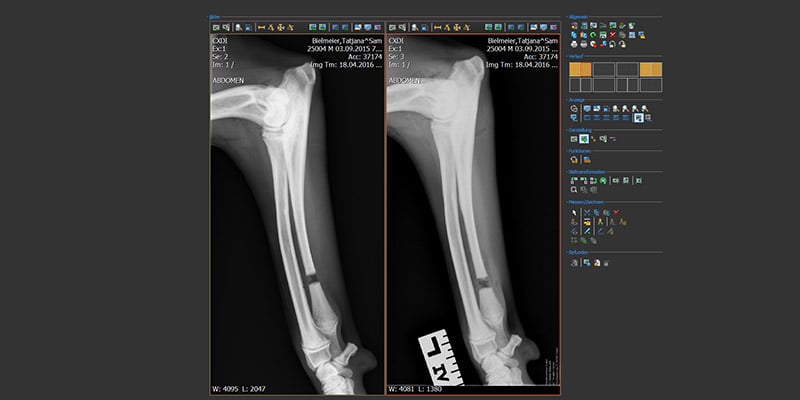

Röntgenologisch:

Besonders im Anfangsstadium ist eine Pathologie im Ellbogengelenk röntgenologisch nicht immer einfach zu beurteilen. Daher spielt die Qualität der Bilder eine sehr entscheidende Rolle. Aber auch mit der besten radiologischen Auflösung sind viele der Veränderungen im Anfangsstadium nur mit weiterführenden Untersuchungen wie mit einem CT zu erkennen.